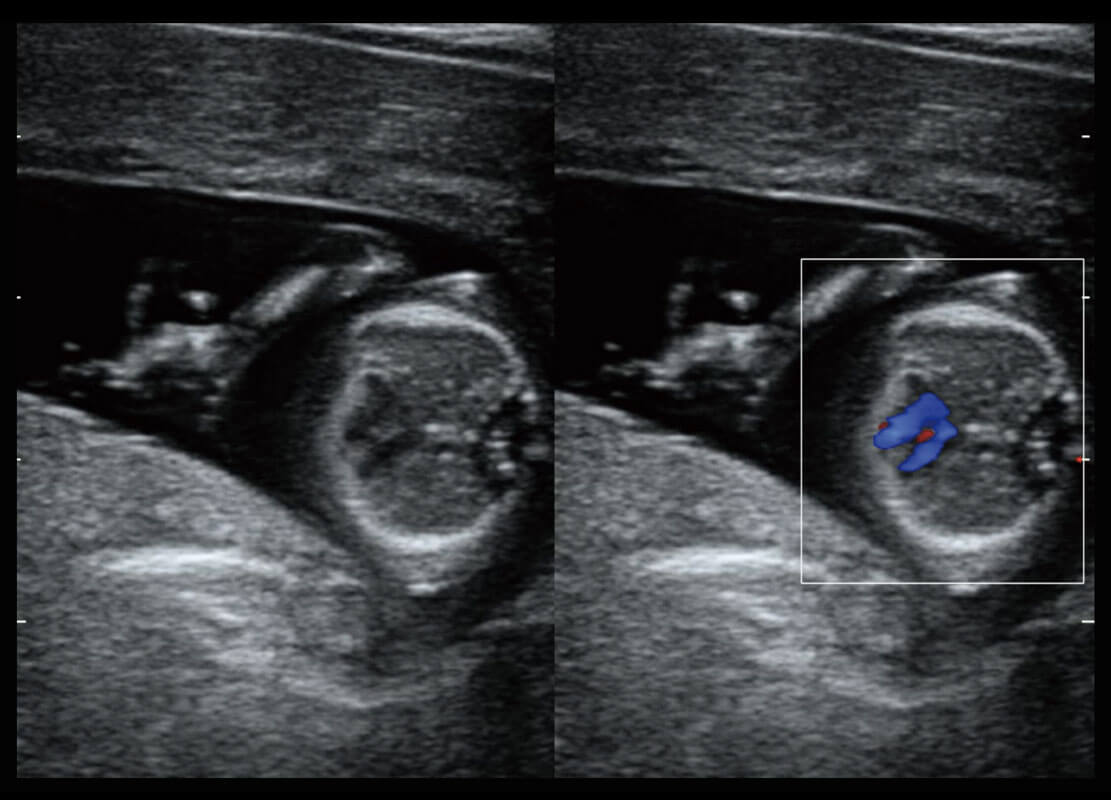

P60搭载一系列胎儿心脏成像技术,实现精细的胎儿心脏评估。

四腔切面

四腔心血流